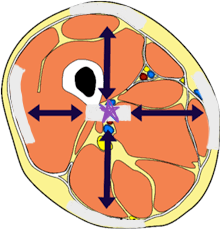

transverse plane